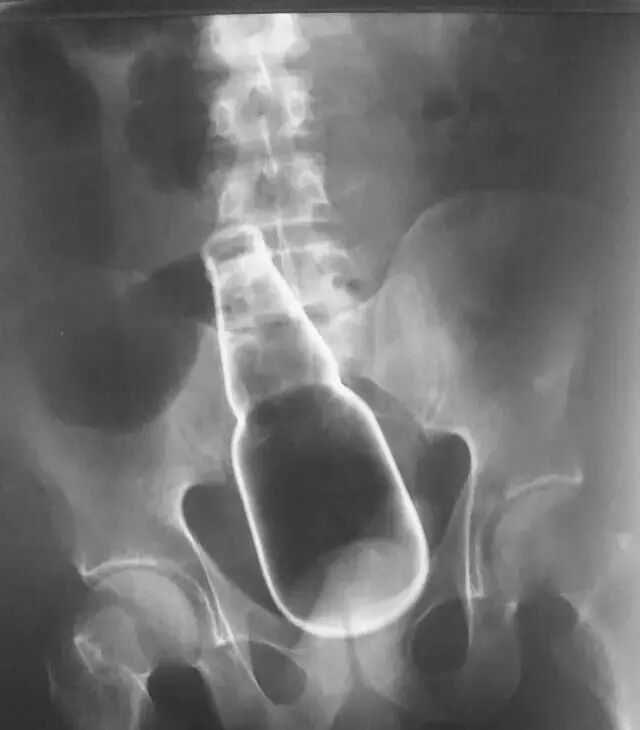

有壮汉一脸正气地说:“医生,我坐到矿泉水瓶了”,结果CT一拍,瓶身深入腹地,全科医生排队围观;